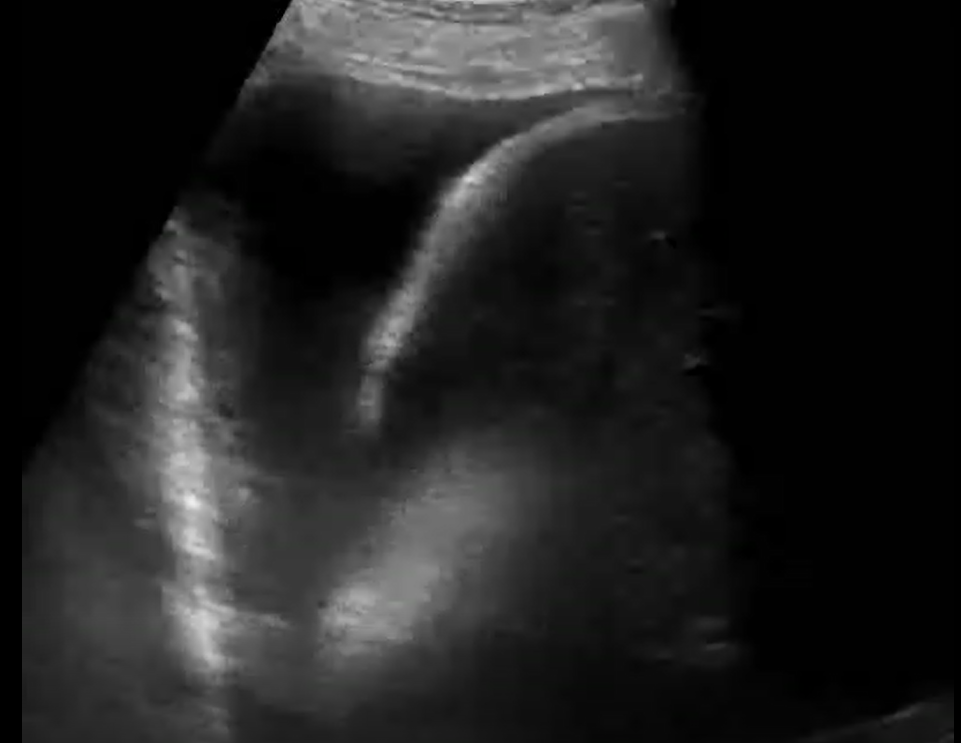

Ultrason cihazlarından alınan videolar kullanılarak derin öğrenme ve video işleme tabanlı bir model oluşturulmuştur. Geliştirilen model COVID-19 hastalarından alınan Akciğer Ultrason (LUS) kayıtlarını; sağlıklı kontrol, bakteriyel pnömoni ve viral pnömoniden başarılı bir şekilde ayırt edebilmektedir. Tasarlanan bu eğitilmiş model sayesinde COVID-19 sınıflandırılması geliştirilen web tabanlı yazılım prototiplemesi ile yapılabilmektedir.